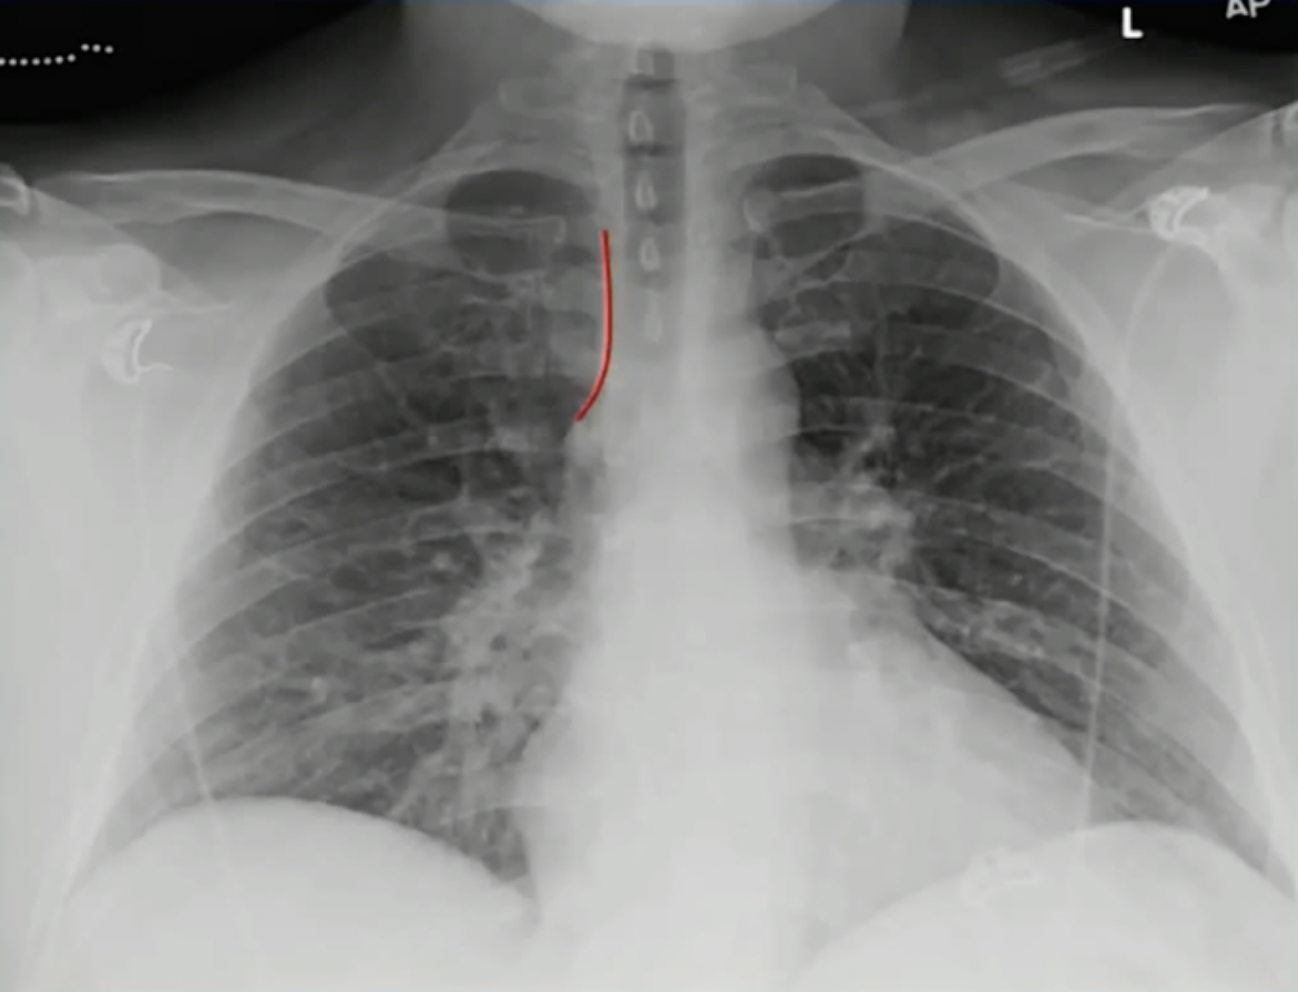

# 正位